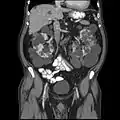

Polycystic kidneys

Autosomal dominant polycystic kidney disease (ADPKD) is one of the most common, life-threatening inherited human disorders and the most common hereditary kidney disease.[1][2] It is associated with large interfamilial and intrafamilial variability, which can be explained to a large extent by its genetic heterogeneity and modifier genes.[1] It is also the most common of the inherited cystic kidney diseases — a group of disorders with related but distinct pathogenesis, characterized by the development of renal cysts and various extrarenal manifestations, which in case of ADPKD include cysts in other organs, such as the liver, seminal vesicles, pancreas, and arachnoid membrane, as well as other abnormalities, such as intracranial aneurysms and dolichoectasias, aortic root dilatation and aneurysms, mitral valve prolapse, and abdominal wall hernias.[1][3][4] Over 50% of patients with ADPKD eventually develop end stage kidney disease and require dialysis or kidney transplantation.[1][5] ADPKD is estimated to affect at least one in every 1000 individuals worldwide, making this disease the most common inherited kidney disorder with a diagnosed prevalence of 1:2000 and incidence of 1:3000-1:8000 in a global scale.[6][7][8][9][10]

Clinically, the insidious increase in the number and size of renal cysts translates as a progressive increment in kidney volume.[1][24] Studies led by Mayo Clinic professionals established that the total kidney volume (TKV) in a large cohort of ADPKD patients was 1060 ± 642ml with a mean increase of 204ml over three years, or 5.27% per year in the natural course of the disease, among other important, novel findings that were extensively studied for the first time.[33]

Usually, the diagnosis of ADPKD is initially performed by renal imaging using ultrasound, CT scan, or MRI.[34] However, molecular diagnostics can be necessary in the following situations: 1- when a definite diagnosis is required in young individuals, such as a potential living related donor in an affected family with equivocal imaging data;[34] 2- in patients with a negative family history of ADPKD, because of potential phenotypic overlap with several other kidney cystic diseases;[34] 3- in families affected by early-onset polycystic kidney disease, since in this cases hypomorphic alleles and/or oligogenic inheritance can be involved;[34][35] and 4- in patients requesting genetic counseling, especially in couples wishing a pre-implantation genetic diagnosis.[34][36]

In ADPKD patients, gradual cyst development and expansion result in kidney enlargement, and during the course of the disease, glomerular filtration rate remains normal for decades before kidney function starts to progressively deteriorate, making early prediction of renal outcome difficult.[81] The CRISP study,[33][44] mentioned in the treatment section above, contributed to build a strong rationale supporting the prognostic value of total kidney volume (TKV) in ADPKD; TKV (evaluated by MRI) increases steadily and a higher rate of kidney enlargement correlated with accelerated decline of GFR, while patient height-adjusted TKV (HtTKV) ≥600 ml/m predicts the development of stage 3 chronic kidney disease within 8 years.[81]

Besides TKV and HtTKV, the estimated glomerular filtration rate (eGFR) has also been tentatively used to predict the progression of ADPKD.[81] After the analysis of CT or MRI scans of 590 patients with ADPKD treated at the Mayo Translational Polycystic Kidney Disease Center, Irazabal and colleagues developed an imaging-based classification system to predict the rate of eGFR decline in patients with ADPKD.[81][44] In this prognostic method, patients are divided into five subclasses of estimated kidney growth rates according to age-specific HtTKV ranges (1A, <1.5%; 1B, 1.5–3.0%; 1C, 3.0–4.5%; 1D, 4.5–6.0%; and 1E, >6.0%) as delineated in the CRISP study.[81][44] The decline in eGFR over the years following initial TKV measurement is significantly different between all five patient subclasses, with those in subclass 1E having the most rapid decline.[81] Some of the most common causes of death in patients with ADPKD are various infections (25%), a ruptured berry aneurysm (15%), or coronary/hypertensive heart disease (40%).[82]